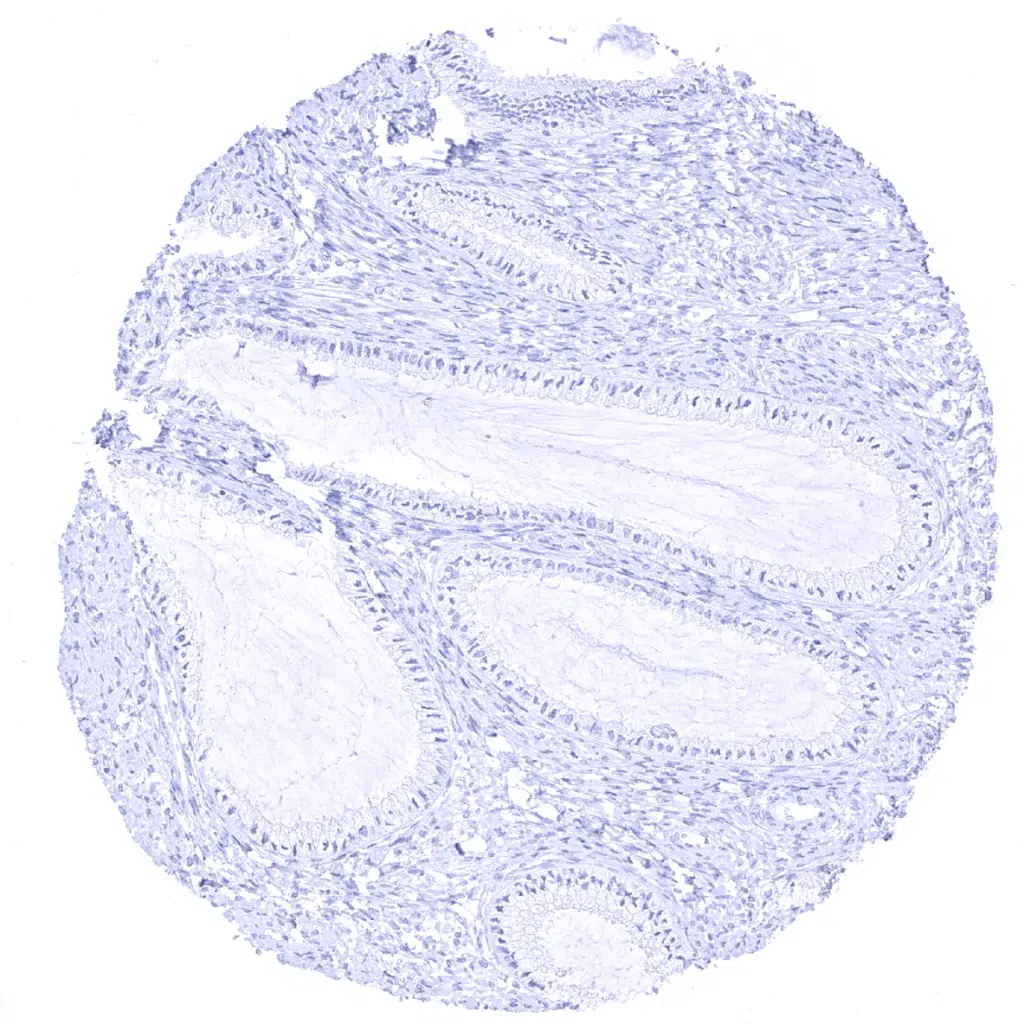

Ectocervix - Cytokeratin 13 immunostaining is strong in all supra-basal cell layers of non-keratinizing squamous epithelium but weak or absent in basal cells.